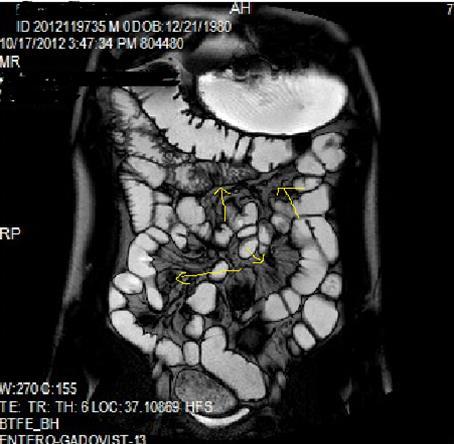

Figure 1a.Diffuse mucosal involvement and increased wall thickness with loss of valvula conniventes in the ileal segments on T2W coronal images after OCA administration, seen on 30 years old female with moderate Crohn’s disease.

Figure 1b.Diffuse bowel wall enhancement in the small intestine due to Crohn’s disease on the Post-contrast T1W coronal sequence.